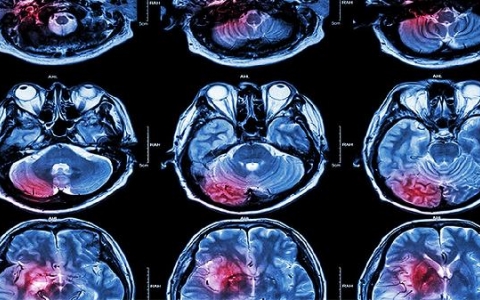

如何治疗急性脑梗死

如何治疗急性脑梗死?脑梗死对人类的影响特别大,当患者及时治疗脑梗死会导致头痛、头晕等,严重也会出现斜嘴歪、肢体水肿等严重危害,因此当患者突然出现急性脑梗死时,必

轻微脑溢血怎么治疗

脑溢血对于中老年人来说是多发的一种急性脑血管病,要知道这种疾病与高血压有着密切的关系,所以对于有吧高血压的患者,在生活中要随时观察自己的身体健康情况,如果有脑溢

蛛网膜下腔出血严重吗?

蛛网膜下腔出血严重吗?1、蛛网膜下腔出血多为严重。外伤、动脉瘤、脑血管畸形等原因导致患者脑底部或表面血管破裂,血液直接流入蛛网膜下腔,血液刺激患者脑沟、脑回流等